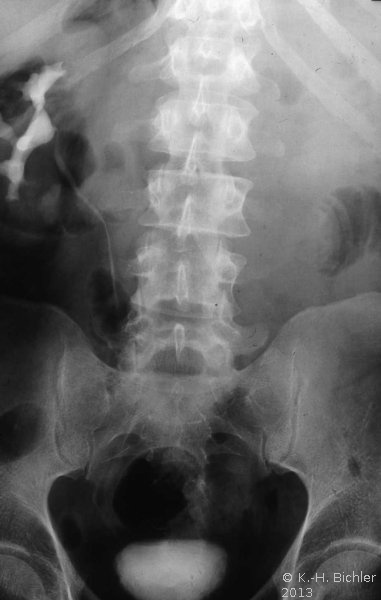

Die Behandlung umfasste neben der perkutanen, transluminalen Dilatation der A. renalis die systemische Behandlung mit Cortison und β-Blocker. Unter dieser Behandlung kam es zur Verbesserung der linksseitigen Nierenfunktion auf 30%. Das AUR zeigte eine zeitgerechte Kontrastmittelausscheidung (Abbildung 20). Im weiteren Verlauf ist evtl. eine neuerliche Dilatation erforderlich bzw. eine operative Versorgung der Nierenarterienstenose.